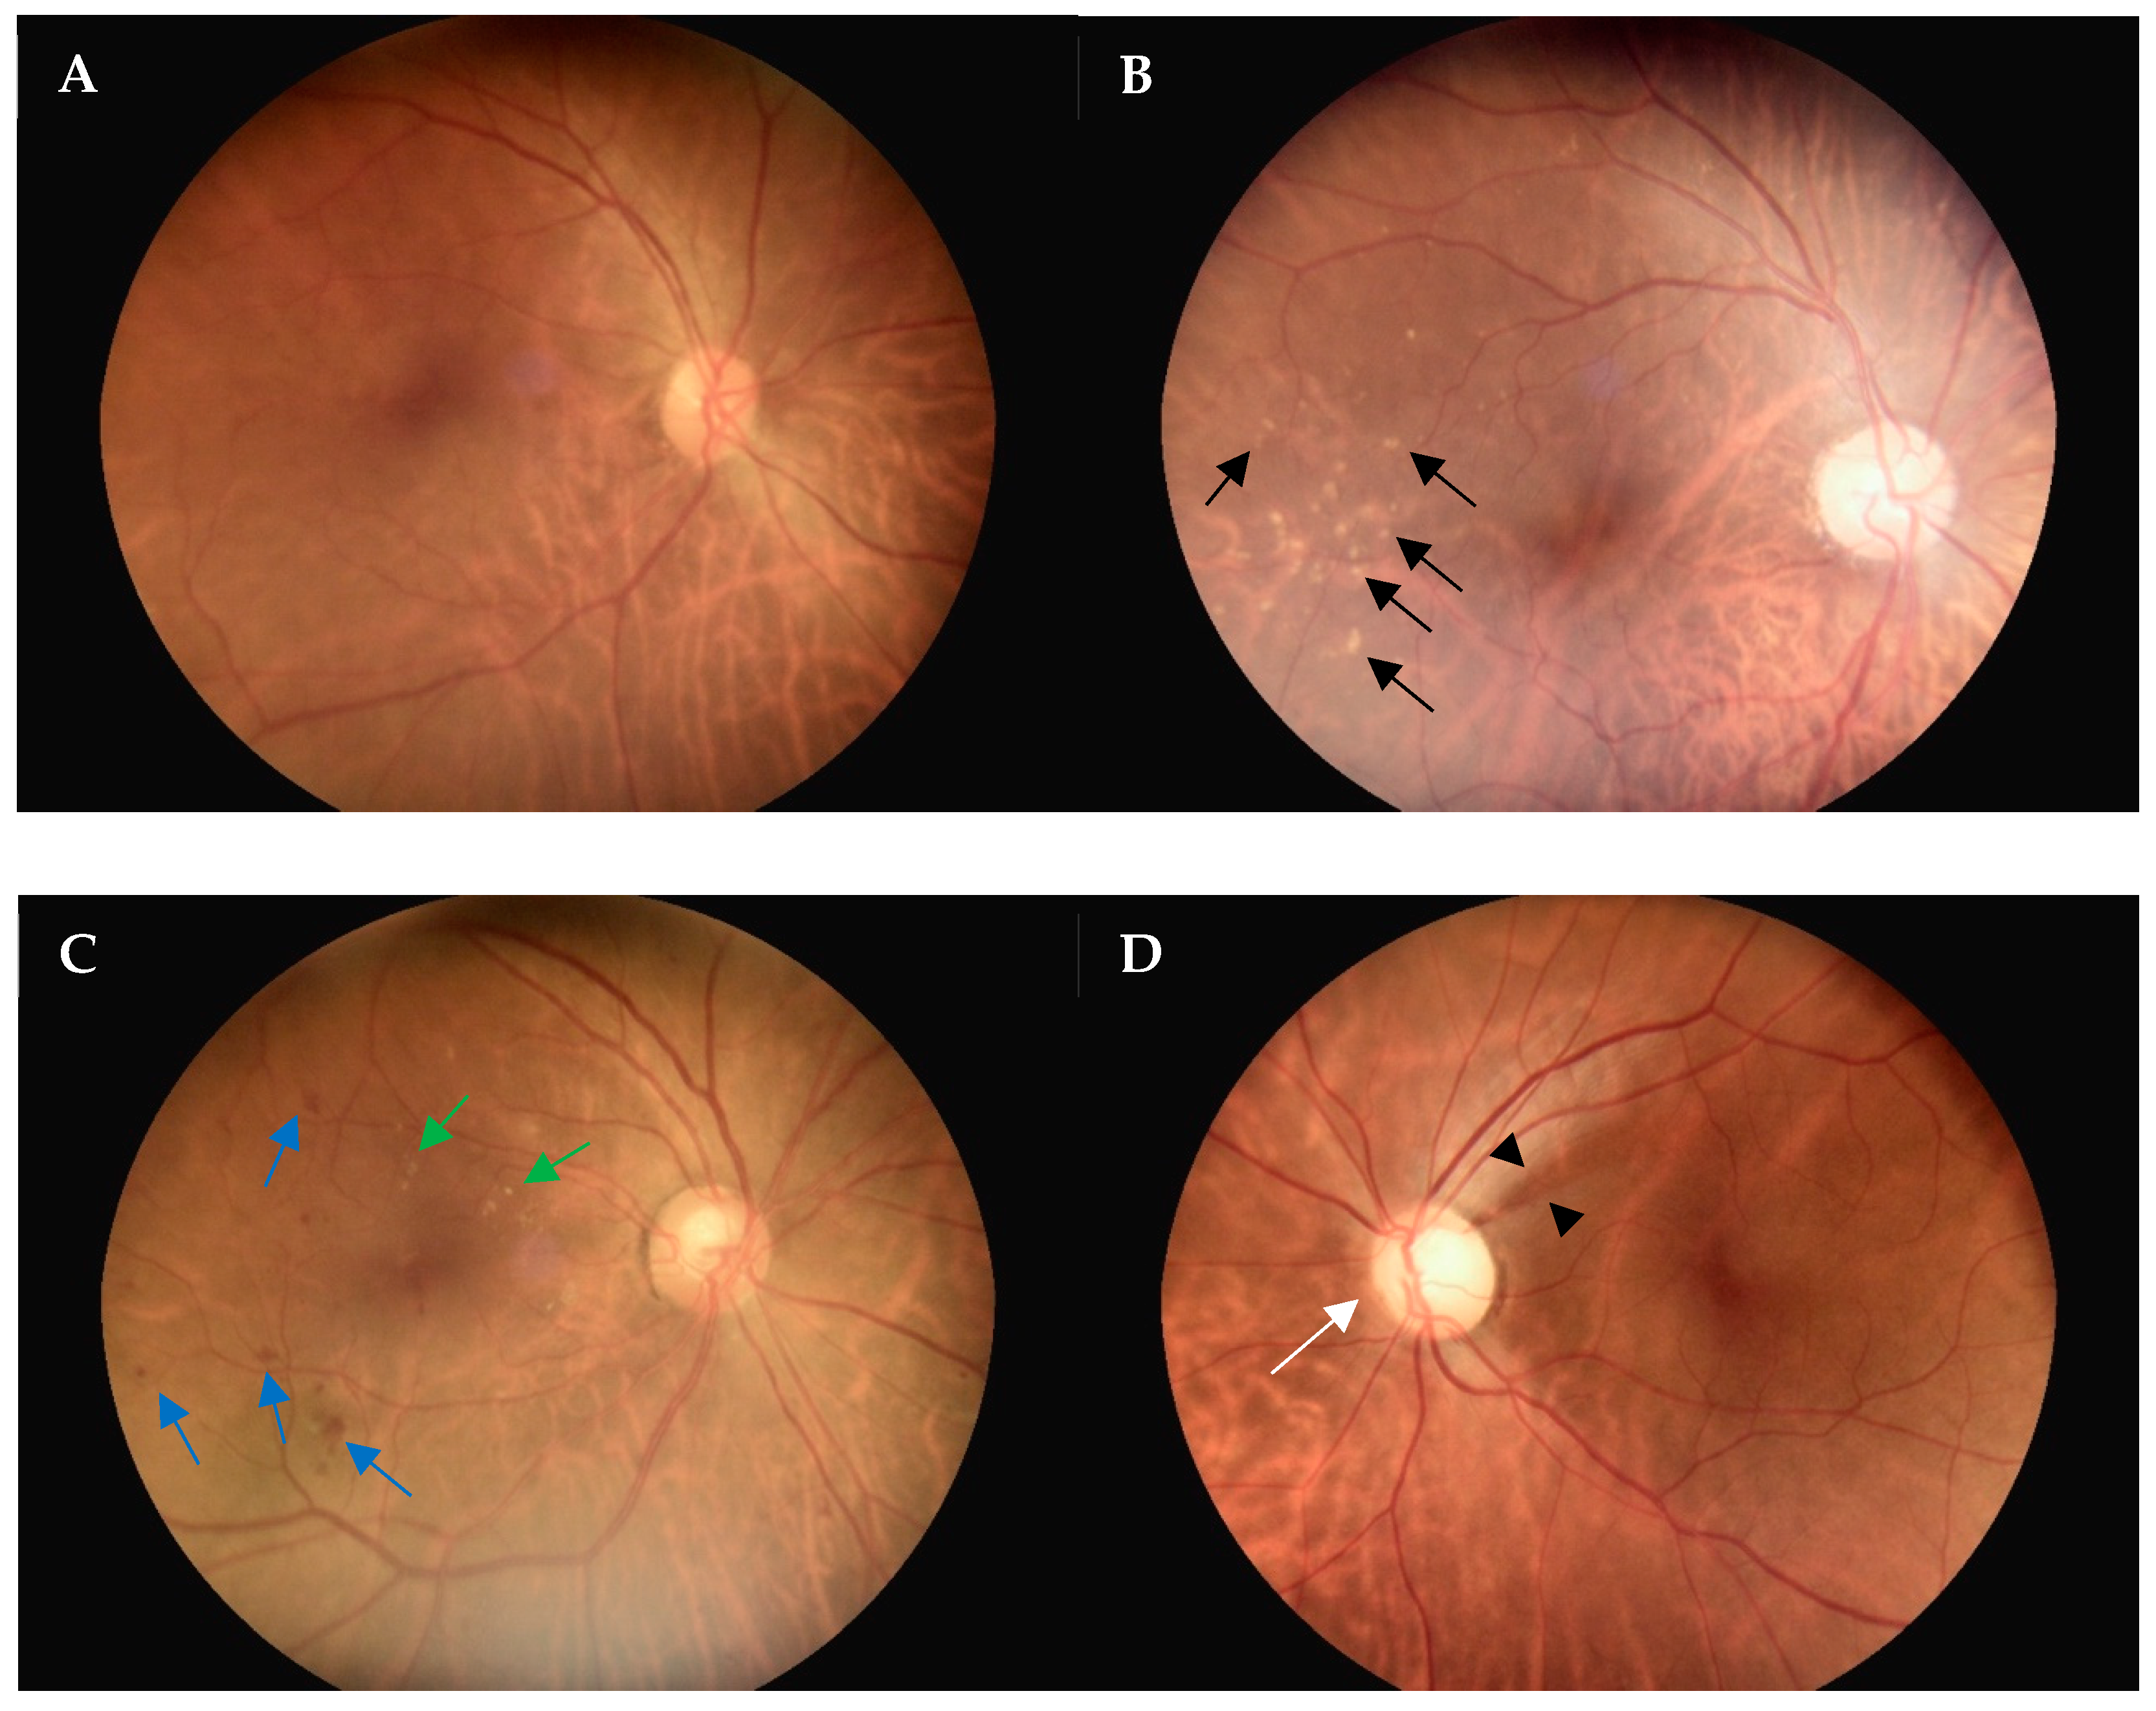

3.3. Evaluation of Fundoscopy Image Quality

3.4. Diagnostic Concordance of the Referrals